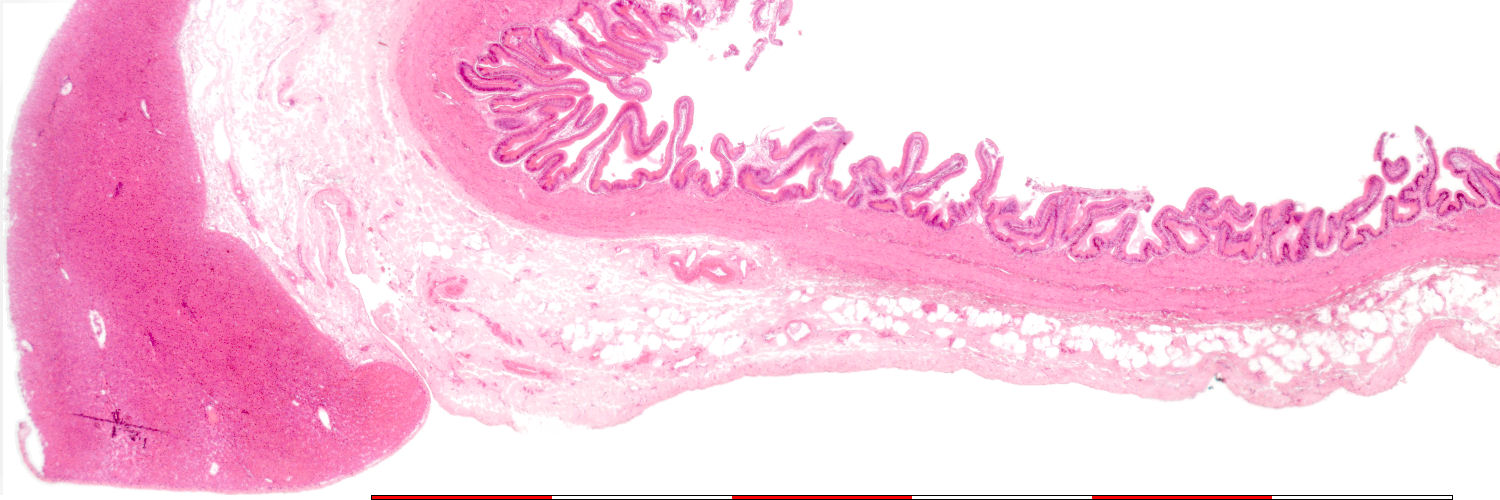

Date: 24 Oktober 2008

© mei 2008 marius loots